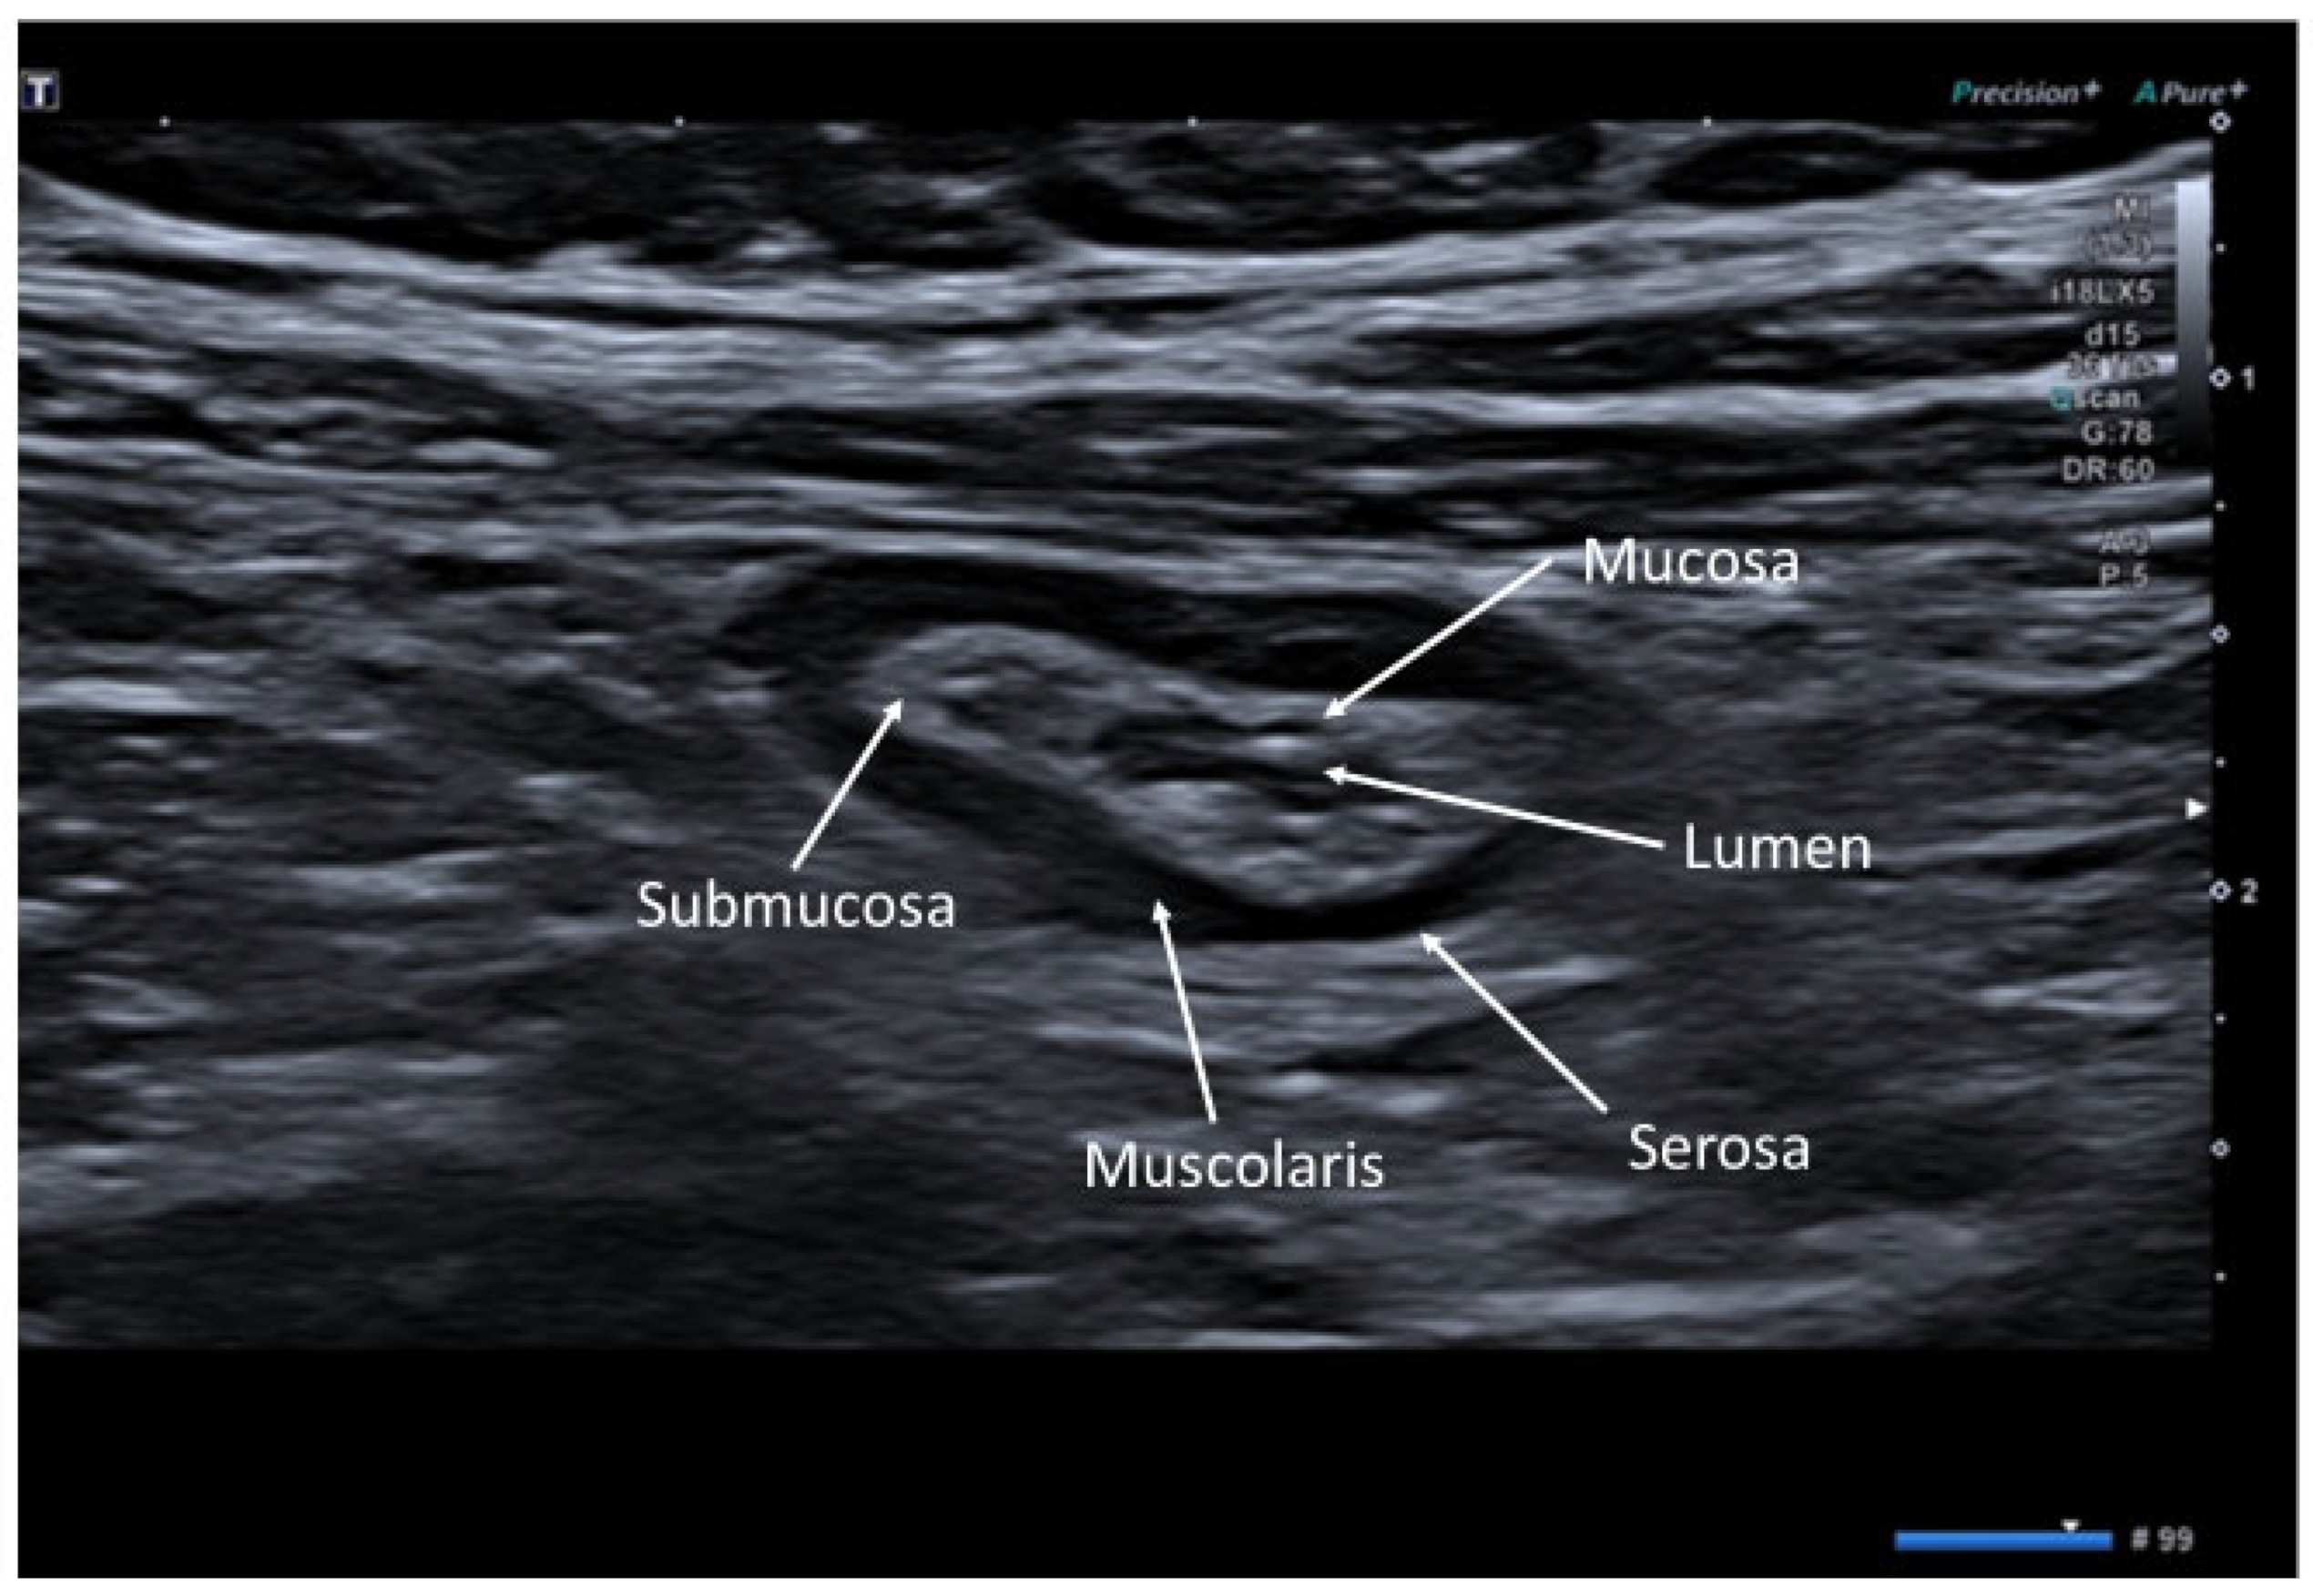

2. Ultrasonographic Anatomy of Gastrointestinal Tract